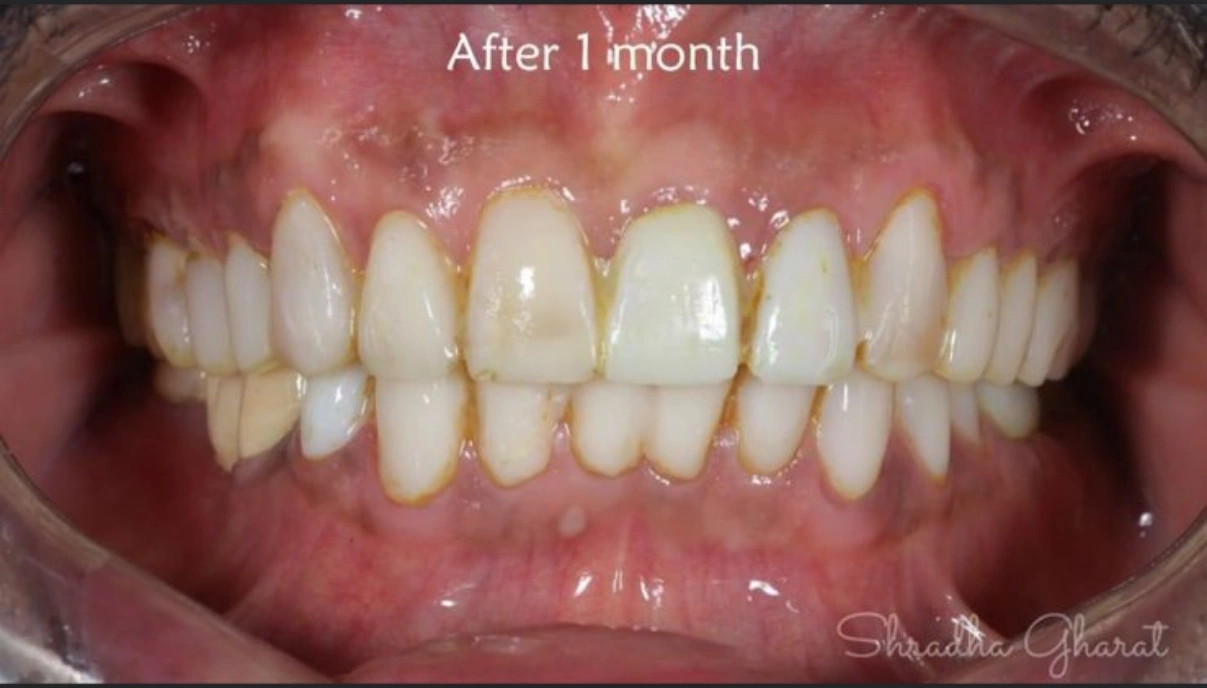

Full mouth rehabilitation (FMR) is a treatment plan for restoring function and function tolerance of dentition after surgery or dental restoration. It aims to restore dentition to the optimal point of function and esthetics of a healthy mouth. The treatment plan provides patients with a permanent smile that looks natural and bright.

Full mouth rehabilitation can improve the overall health of the patient by improving their oral health, maximizing their dental treatment options, and enhancing their quality of life. So, if you are looking for full mouth rehabilitation treatment in Navi Mumbai, Om Dental Clinic is your best bet. Contact us today and get a consultation done with our dentist.